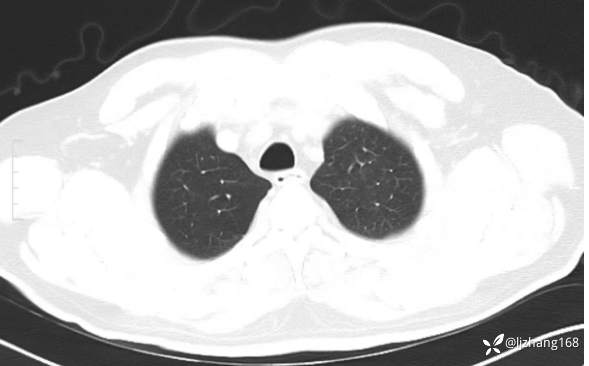

中年男患,右肺团片影,炎症0R肿瘤?

患者年龄:47岁

主诉:咳嗽、 咳痰伴气短20+天

简要病史: 20+天前患者因受凉后出现阵发性咳嗽,咳少量白色粘痰,痰易咳出,伴活动后气短,伴纳差、乏力、全身酸痛,伴多汗,无痰中带血及咯血,无发热、畏寒及寒战,无潮热、盗汗,无夜间阵发性呼吸困难及端坐呼吸,无声嘶,无头晕、头痛,无黑矇、晕厥及意识障碍,无腹痛、呕血及黑便等不适,遂就诊于当地医院予以输液等治疗后未见明显好转(具体诊疗不详),现为进一步诊治就诊于我院门诊,以“右肺占位”收入我科。病来饮食欠佳,近期体重下降(具体不详)。既往糖尿病病史7+年,未规律监测血糖,血糖控制不佳。否认“高血压、冠心病及慢性肾脏病”等慢性疾病史。否认“肝炎、结核、伤寒”等传染病史。否认食物、药物过敏史。否认外伤、输血史,预防接种史不详。

辅助检查:糖化血红蛋白12.3%。肺炎支原体IgG、IgM、呼吸道合胞病毒均未见明显异常。胸部CT:右肺上叶阻塞性肺炎。